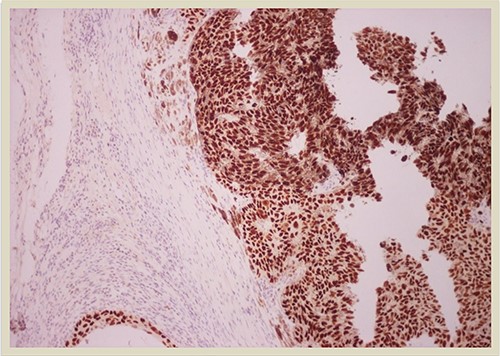

p63 × 10: p63 immunostain confirms the presence of squamous cell carcinoma component (×10 magnification).